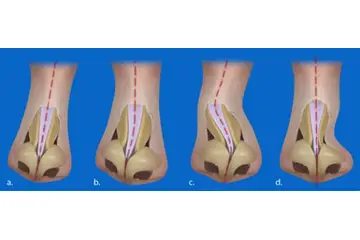

Diz Kıkırdak Hasarının Tanısı Diz kıkırdak hasarının tanısı, genellikle bir ortopedi uzmanı tarafından konulur. Tanı sürecinde şu yöntemler kullanılabilir:

Diz Kıkırdak Hasarının Tedavi Yöntemleri Diz kıkırdak hasarının tedavisi, hasarın ciddiyetine ve bireyin genel sağlık durumuna bağlı olarak değişir. Tedavi yöntemleri arasında şunlar bulunmaktadır: